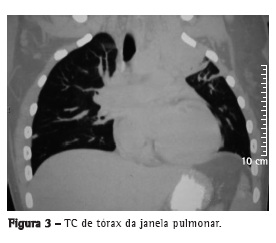

Foi encaminhada ao serviço de cirurgia torácica para investigação diagnóstica. A ressonância magnética mostrava uma lesão de contornos irregulares com captação de contraste, medindo aproximadamente 9,2 × 7,2 × 6,0 cm, ocupando a totalidade do lobo superior esquerdo, com invasão mediastinal e da parede torácica, e envolvendo a artéria carótida comum esquerda, a subclávia esquerda e parte do arco aórtico (Figura 1). Foi submetida à TC de tórax, a qual mostrou invasão das referidas estruturas e aderência da lesão aos corpos vertebrais, com invasão da fossa supraclavicular esquerda (Figuras 2 e 3).

Não há sinais radiológicos para a actinomicose torácica,(4) podendo a radiografia de tórax mimetizar uma grande variedade de doenças, desde um infiltrado pulmonar, sugerindo uma pneumonia limitada, até um infiltrado micronodular e cavitações pulmonares ou grandes massas, sugerindo neoplasia, sendo o derrame pleural comum.(1,2,4,8,9) A TC de tórax pode revelar envolvimento de parede torácica, do mediastino e da pleura em casos avançados.(1,4,9) Uma imagem difusa sem respeitar limites anatômicos é altamente sugestiva de actinomicose pulmonar.(4)